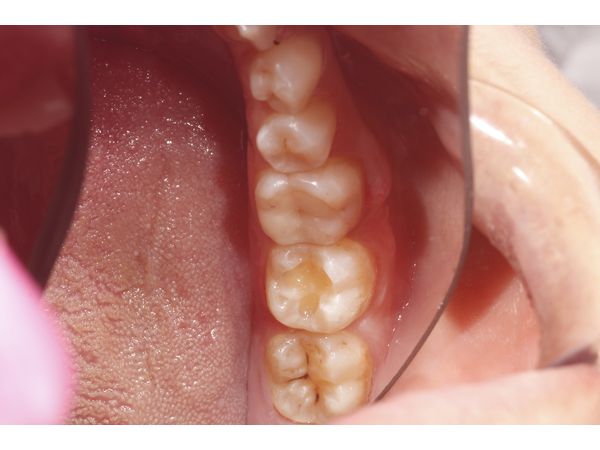

При осмотре на левом нижнем моляре (36-м зубе) наблюдалась композитная пломба, края прилегания которой были нарушены. Десна вокруг зуба покраснела. Рядом находилось отверстие (свищевой ход), из которого сочилось прозрачное содержимое. Простукивание моляра слабоболезненное.